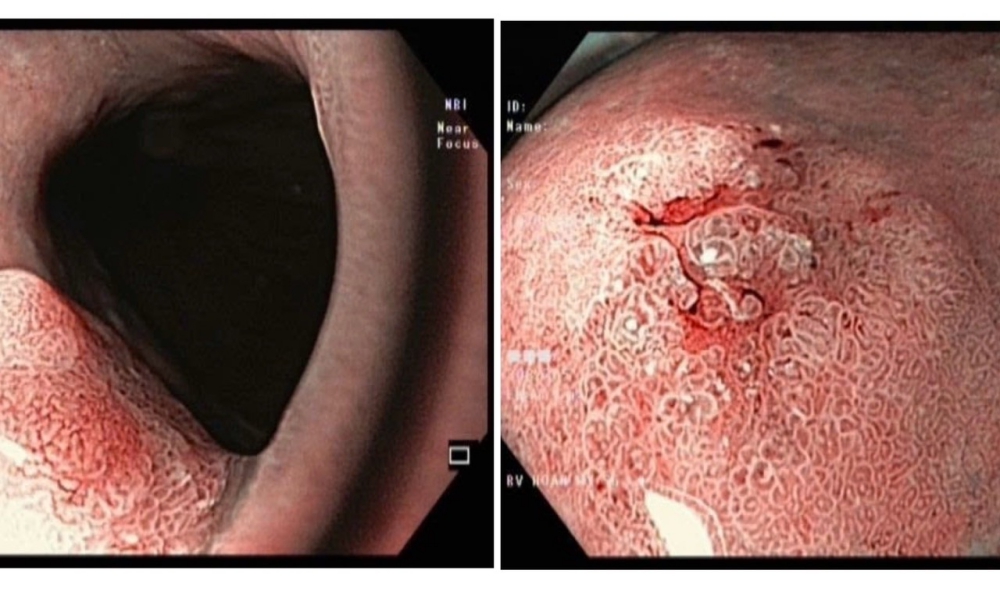

Kỹ thuật hiện đại giúp phát hiện sớm ung thư

Kỹ thuật cắt tách dưới niêm mạc qua nội soi, là bước tiến vượt bậc của y học hiện đại, giúp điều trị triệt để ung thư ở giai đoạn sớm.